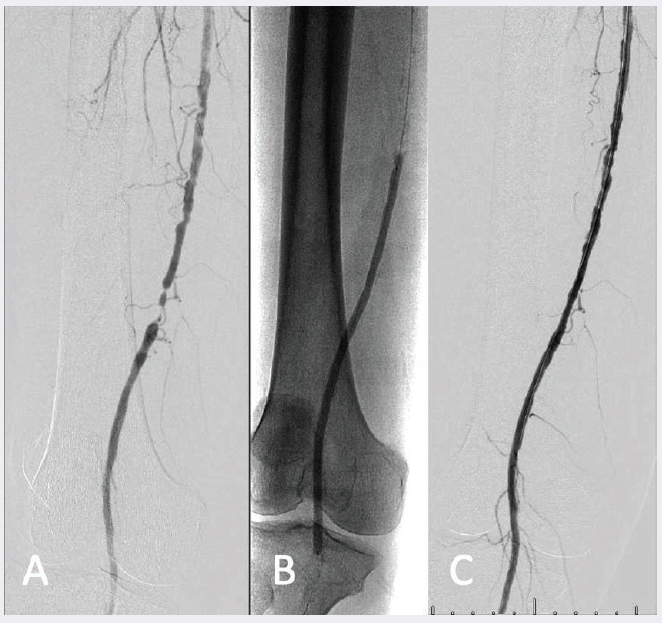

Ultrasound-guided access of the left common femoral artery was obtained, and right lower extremity angiography confirmed the presence of multiple tandem lesions in the right distal SFA and distal popliteal artery in excess of 75% stenosis (Figure 1A), as well as chronic occlusions of the proximal anterior tibial and posterior tibial arteries (Figure 1B). Her dominant infrapopliteal runoff was via a relatively disease-free peroneal artery.

Next, a 6 Fr 65 cm Pinnacle Destination sheath (Terumo) was advanced over the aortic bifurcation to the level of the mid right SFA. Successful wire catheterization of the right anterior tibial artery was achieved with aid of an .018-inch 135 cm TrailBlazer support catheter (Medtronic) and .014-inch Glide Advantage wire (Terumo). A SpiderFX embolic protection device (Medtronic) was placed to the level of the distal anterior tibial artery. A total of four passes of the HawkOne M directional atherectomy system (Medtronic) was performed in the distal femoropopliteal and proximal anterior tibial arteries to serve as vessel preparation (Figure 2A).

Balloon angioplasty of the right distal SFA and popliteal arteries was subsequently performed using a 6 mm x 250 mm IN.PACT Admiral drug-coated PTA balloon catheter (Medtronic) (Figure 2B). Additional balloon angioplasty of the proximal anterior tibial artery was then completed using a 3.0 mm x 120 mm Chocolate PTA balloon catheter (Medtronic) (Figure 2C).

Completion angiography demonstrated a widely patent right distal femoropopliteal segment (Figure 3A) and restoration of 2-vessel infrapopliteal runoff, which included recanalization of the occluded proximal anterior tibial artery (Figure 3B). One-month follow-up duplex noted interval improvement in the right ABI to 0.93, including biphasic waveforms at the ankle in the peroneal and anterior tibial artery distributions. She reported full resolution of her disabling right lower extremity symptoms.